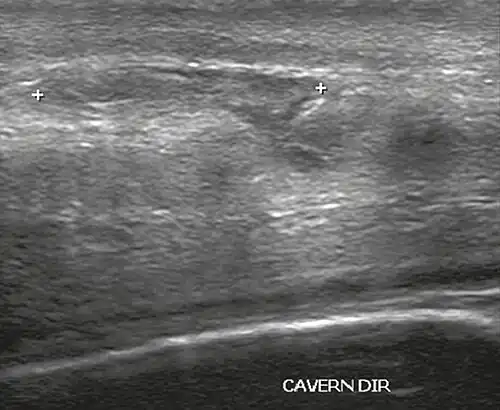

Ultrasound examination is able to depict the tunica albuginea tear in the majority of cases (as a hypoechoic discontinuity in the normally echogenic tunica). In a study on 25 patients, Zare Mehrjardi et al. concluded that ultrasound is unable to find the tear just when it is located at the penile base. In their study magnetic resonance imaging (MRI) accurately diagnosed all of the tears (as a discontinuity in the normally low signal tunica on both T1- and T2-weighted sequences). They concluded that ultrasound should be considered as the initial imaging method, and MRI can be helpful in cases that ultrasound does not depict any tear but clinical suspicions for fracture are still high. In the same study, authors investigated accuracy of ultrasound and MRI for determining the tear location (mapping of fracture) in order to perform a tailored surgical repair. MRI was more accurate than ultrasound for this purpose, but ultrasound mapping was well correlated with surgical results in cases where the tear was clearly visualized on ultrasound exam.[10] The advantage of ultrasound in the diagnosis of penile fracture is unrivaled when its noninvasive, cost-effective, and nonionising nature are considered.[11]

In the ultrasound examination, a lesion of the tunica albuginea presents as an interruption in (loss of continuity of) the echoic line representing it (Figure 4). Small, moderate, or broad hematomas demonstrate the extent of that discontinuity. Intracavernous hematomas, sometimes without the presence of a tunica albuginea fracture, can be observed when there is a lesion of the smooth muscle of the trabeculae surrounding the sinusoid spaces or the subtunical venular plexus.[2]

Figure 4 A: Ultrasound of the penis, right lateral view. Longitudinal section showing rupture of the tunica albuginea with an adjacent 1.92 cm hematoma (between calipers), due to trauma.[2] -